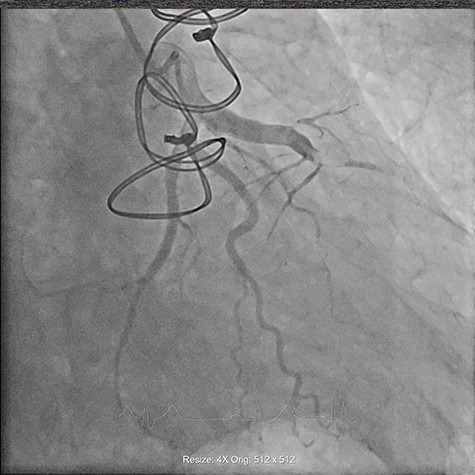

On Day 1 of his admission the patient developed sudden onset chest pain radiating to the back, associated with electrocardiogram features of an anterior ST elevation myocardial infarction (Fig. 1). He was taken for an urgent coronary angiogram, which demonstrated proximal occlusion of the left anterior descending artery (LAD) secondary to coronary artery embolism (Fig. 2). A guidewire was successfully passed into the LAD, and an aspiration-thrombectomy catheter was employed to successfully re-canalize the occluded artery.

Coronary angiogram demonstrating proximally occluded LAD artery.